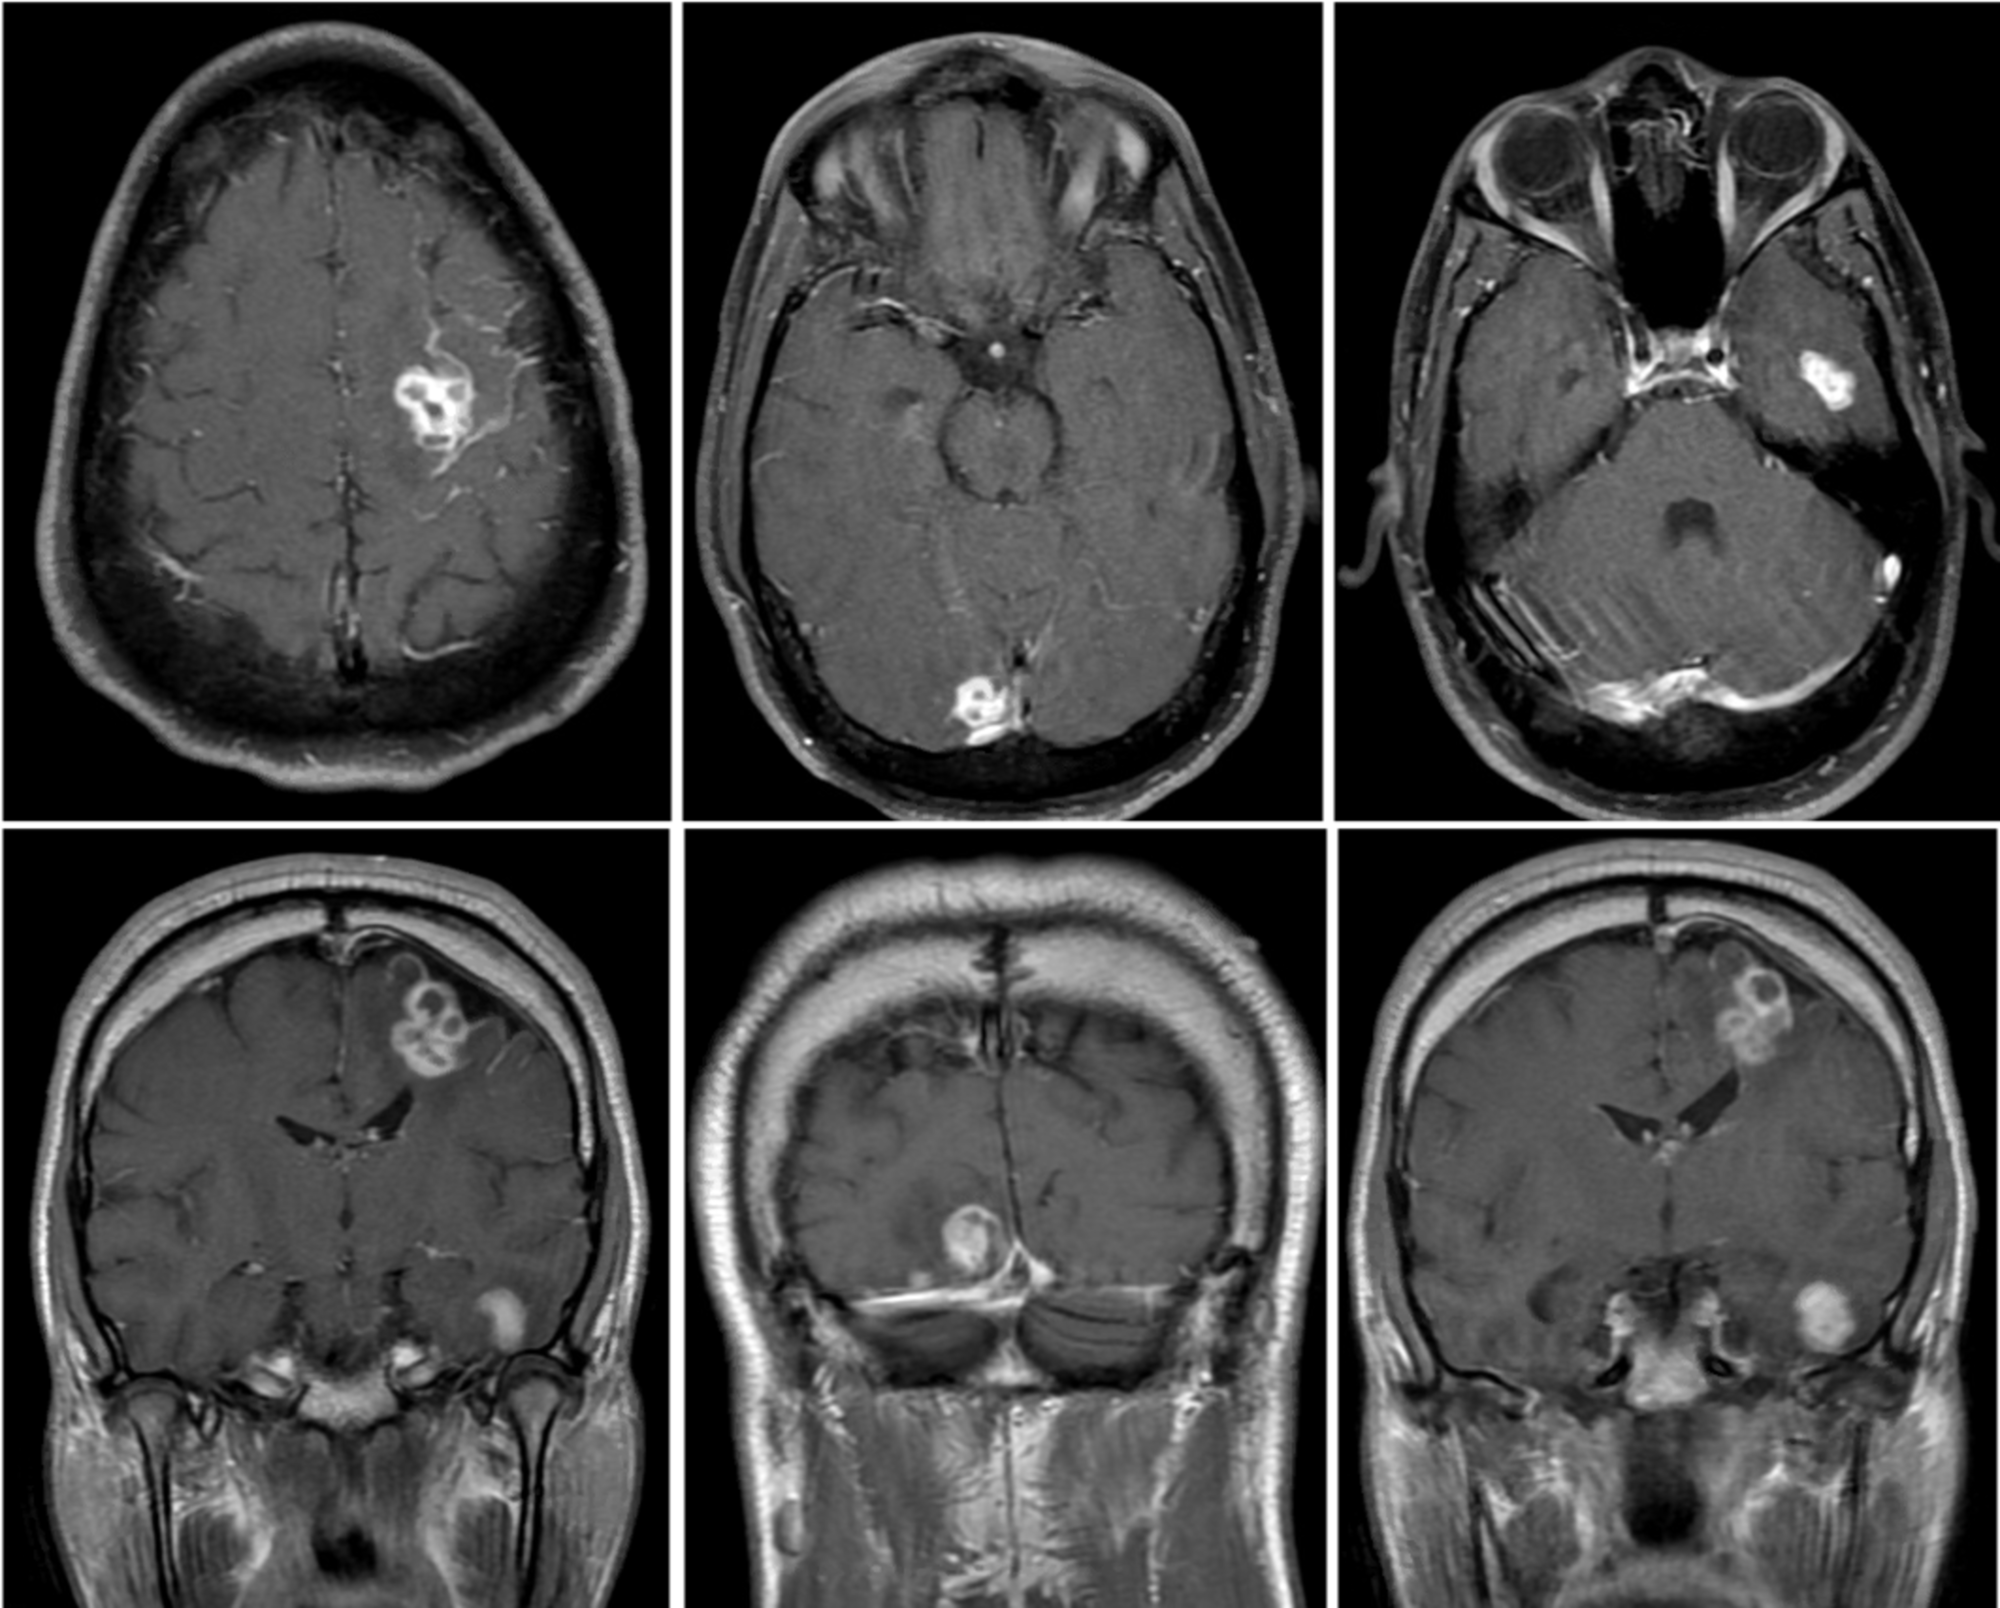

Hiv Brain Lesions Mri . Direct consequence of the hiv virus. Hiv/aids affects the cns by one of four mechanisms: Magnetic resonance imaging (mri) brain redemonstrated bilateral cerebral and cerebellar enhancing lesions, atypical for toxoplasmosis,. Magnetic resonance imaging (mri) can improve the outlook for people with hiv through early diagnosis and prompt treatment. Ct and mri typically reveal multiple enhancing lesions with perifocal oedema and mass effect in the basal ganglia and. While hiv infection is known to cause widespread disruptions in the brain, different magnetic resonance imaging (mri) modalities. This topic will address the differential diagnosis and initial clinical and diagnostic evaluation of central nervous. Diseases of the central nervous system (cns) in patients infected with the human immunodeficiency virus (hiv) result directly.

Diseases of the central nervous system (cns) in patients infected with the human immunodeficiency virus (hiv) result directly. Magnetic resonance imaging (mri) brain redemonstrated bilateral cerebral and cerebellar enhancing lesions, atypical for toxoplasmosis,. Hiv/aids affects the cns by one of four mechanisms: Ct and mri typically reveal multiple enhancing lesions with perifocal oedema and mass effect in the basal ganglia and. While hiv infection is known to cause widespread disruptions in the brain, different magnetic resonance imaging (mri) modalities. This topic will address the differential diagnosis and initial clinical and diagnostic evaluation of central nervous. Direct consequence of the hiv virus. Magnetic resonance imaging (mri) can improve the outlook for people with hiv through early diagnosis and prompt treatment.

Hiv Brain Lesions Mri Ct and mri typically reveal multiple enhancing lesions with perifocal oedema and mass effect in the basal ganglia and. Magnetic resonance imaging (mri) brain redemonstrated bilateral cerebral and cerebellar enhancing lesions, atypical for toxoplasmosis,. This topic will address the differential diagnosis and initial clinical and diagnostic evaluation of central nervous. Direct consequence of the hiv virus. Ct and mri typically reveal multiple enhancing lesions with perifocal oedema and mass effect in the basal ganglia and. Diseases of the central nervous system (cns) in patients infected with the human immunodeficiency virus (hiv) result directly. Magnetic resonance imaging (mri) can improve the outlook for people with hiv through early diagnosis and prompt treatment. While hiv infection is known to cause widespread disruptions in the brain, different magnetic resonance imaging (mri) modalities. Hiv/aids affects the cns by one of four mechanisms:

Ringenhancing cerebral lesions Cleveland Clinic Journal of Medicine Hiv Brain Lesions Mri Ct and mri typically reveal multiple enhancing lesions with perifocal oedema and mass effect in the basal ganglia and. This topic will address the differential diagnosis and initial clinical and diagnostic evaluation of central nervous. Magnetic resonance imaging (mri) brain redemonstrated bilateral cerebral and cerebellar enhancing lesions, atypical for toxoplasmosis,. Hiv/aids affects the cns by one of four mechanisms: Magnetic. Hiv Brain Lesions Mri.

[PDF] Concentric and Eccentric Target MRI Signs in a Case of HIV Hiv Brain Lesions Mri Magnetic resonance imaging (mri) brain redemonstrated bilateral cerebral and cerebellar enhancing lesions, atypical for toxoplasmosis,. Hiv/aids affects the cns by one of four mechanisms: Ct and mri typically reveal multiple enhancing lesions with perifocal oedema and mass effect in the basal ganglia and. This topic will address the differential diagnosis and initial clinical and diagnostic evaluation of central nervous. Direct. Hiv Brain Lesions Mri.

Multiple ring enhancing lesions in brain MRI of a patient with AIDS Hiv Brain Lesions Mri Hiv/aids affects the cns by one of four mechanisms: While hiv infection is known to cause widespread disruptions in the brain, different magnetic resonance imaging (mri) modalities. This topic will address the differential diagnosis and initial clinical and diagnostic evaluation of central nervous. Magnetic resonance imaging (mri) brain redemonstrated bilateral cerebral and cerebellar enhancing lesions, atypical for toxoplasmosis,. Magnetic resonance. Hiv Brain Lesions Mri.

Ring enhancing brain lesions in a patient with Acquired Hiv Brain Lesions Mri This topic will address the differential diagnosis and initial clinical and diagnostic evaluation of central nervous. Hiv/aids affects the cns by one of four mechanisms: Magnetic resonance imaging (mri) brain redemonstrated bilateral cerebral and cerebellar enhancing lesions, atypical for toxoplasmosis,. Direct consequence of the hiv virus. Magnetic resonance imaging (mri) can improve the outlook for people with hiv through early. Hiv Brain Lesions Mri.

Toxoplasmosis and tuberculosis brain lesions in HIV/AIDS Hiv Brain Lesions Mri While hiv infection is known to cause widespread disruptions in the brain, different magnetic resonance imaging (mri) modalities. Magnetic resonance imaging (mri) can improve the outlook for people with hiv through early diagnosis and prompt treatment. Direct consequence of the hiv virus. Magnetic resonance imaging (mri) brain redemonstrated bilateral cerebral and cerebellar enhancing lesions, atypical for toxoplasmosis,. Hiv/aids affects the. Hiv Brain Lesions Mri.